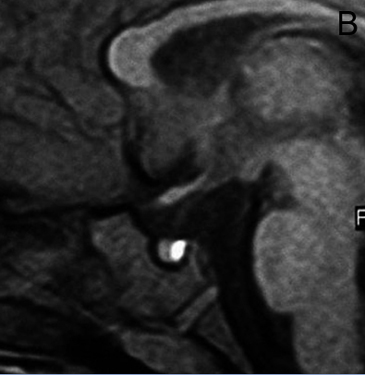

A diferencia de la tomografia computada, que emplea tubos de rayos X, la RM no utiliza radiaciones ionizantes, lo que es una ventaja a considerar en los pacientes pediátricos y en las mujeres embarazadas. La RM tiene una excelente resolución espacial y de tejidos blandos; por ejemplo permite precisar la presencia o ausencia de la neurohipófisis, lo que no es posible con la Tomografia Computada5-7. Con la TAC, con o sin medio de contraste yodado, es posible detectar microadenomas y macroadenomas pituitarios (Figuras 1A y 1B); sin embargo, en los macroadenomas puede ser difícil distinguir las relaciones del tumor con el quiasma óptico, o definir la invasión del seno cavernoso. Además, los artefactos producidos por amalgamas dentales deterioran las imágenes y la dificultad para lograr posiciones cómodas para los pacientes, con el fin de obtener cortes coronales directos, limitan la utilidad de la TAC.

Figura 1A y B. TAC con contraste yodado, corte coronal, muestra un microadenoma lateralizado a izquierda (punta de flecha). Control a los 2 años. TAC con contraste yodado, corte coronal, demuestra aumento de volumen del microadenoma, lo que es infrecuente de observar en clínica (punta de flecha).